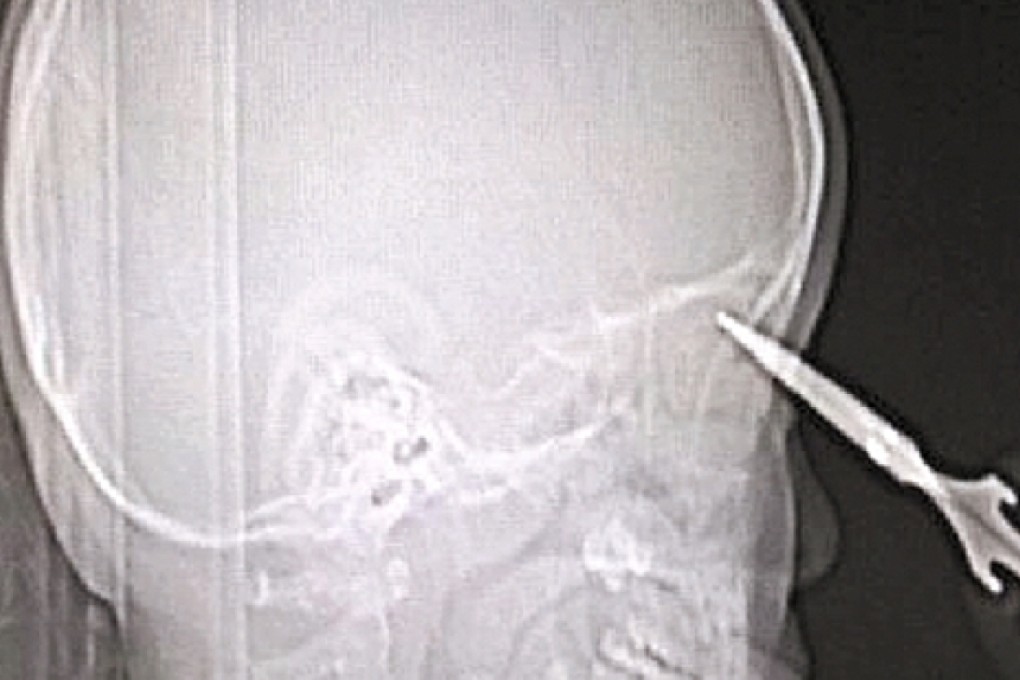

Chinese boy, aged 3, unharmed after inserting scissors up his nose

CT scans at the hospital showed the tip of the scissors barely reaching the boy’s brain tissues through the nose.